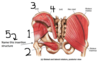

- Body of ilium

- ASIS

- AIIS

- Pubic tubercle

- Body of pubis

- Inferior ramus of pubis

- Ramus of ischium

- Ischial tuberosity

- Body of ischium

- Rim of acetabulum

- Greater sciatic notch

- Gluteus minimus

- Obterator internus

- Gluteus medius

- Gluteus maximus

- Greater trochanter

Iliotibial tract